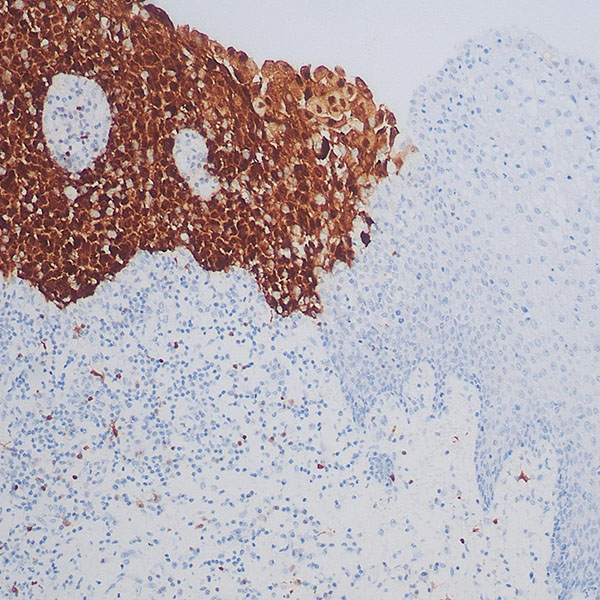

实验结果展示: